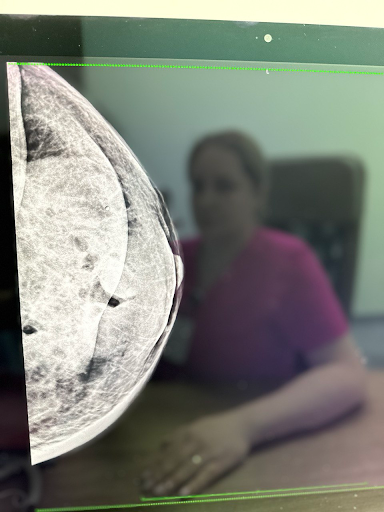

- рентгенологічна – мамографія;

Оскільки рак грудей починається з об’ємних утворень, які можна виявити під час мамографії, УЗД та інших профільних обстежень, жінці потрібно систематично відвідувати лікаря-мамолога і проводити самообстеження. Якісна діагностика дозволить вчасно виявити і вилікувати захворювання ще на ранніх його стадіях.